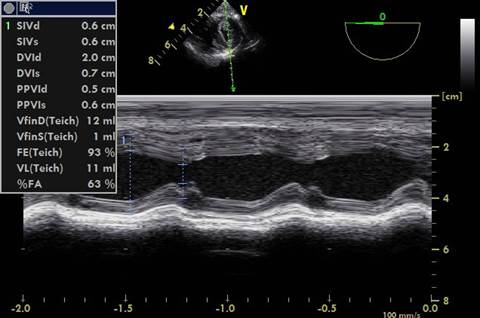

FAC: En plano transgástrico eje corto se implementa modo M lo más transversal posible al ventrículo izquierdo sin tomar músculos papilares. Imagen 2.

FAC: Luego de aplicar el modo M se utilizó el software del ecógrafo para medir las dimensiones en diástole y sístole.